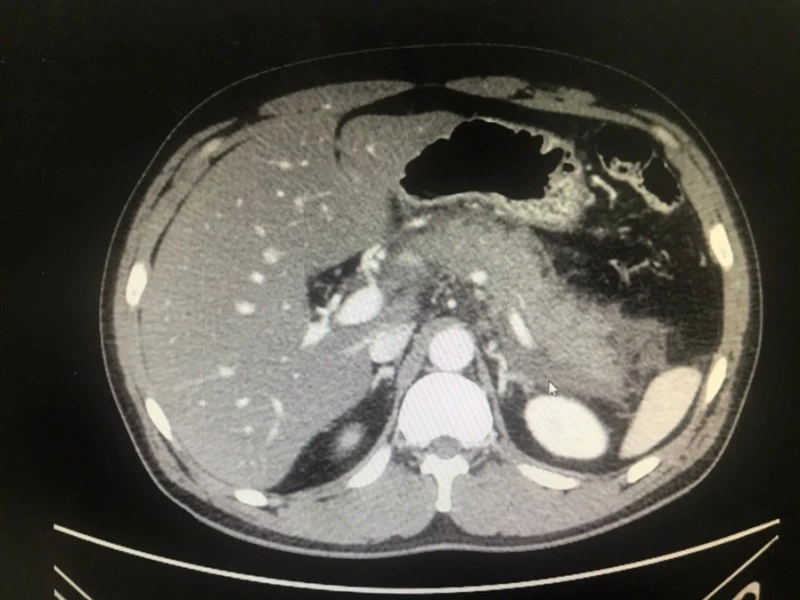

심야에 ER 찾아온 30대 중반 유부남의 (어지간한 약으론 전혀 잡히지 않던) 극심한 복통 원인은 췌장염이었어요. 드높은 리파아제 수치와 복부 CT의 심란한 풍경은 명백한 물증이었습니다.

혈액 검사 결과와 영상 소견을 환자와 보호자에게 상세히 보여주며 따끔하게 훈계했습니다. 반성하는 눈빛으로 고개를 주억거리며 입원은 하셨는데요. 차돌처럼 박힌 습관이 퇴원 후에 완전히 뽑힐 지는 미지수네요. 낚싯바늘은 뽑을 수나 있지, 몹쓸 중독은 남다른 각오 없인 뽑히지도 않잖아요.